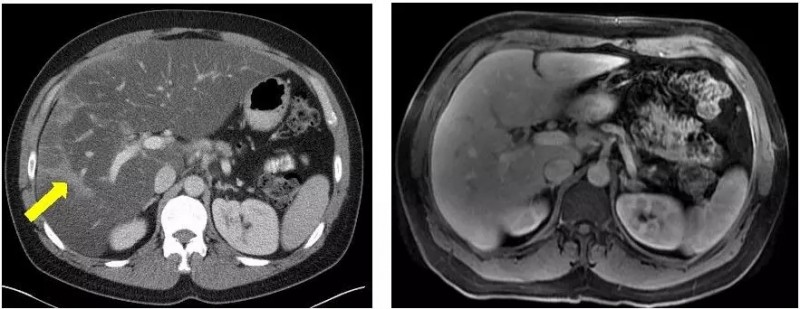

所以,Broman停止了FOLFIRINOX,现在每天服用12粒奥拉帕尼(olaparib),他说不会有副作用。在他使用奥拉帕尼六个月后,MRI和CT扫描显示没有癌症复发,生物标志物水平保持在正常范围。Ng说,只要癌症得到控制,他可以无限期地服用奥拉巴利,因为副作用很小。

FOLFIRINOX治疗5个月病灶明显缩小 vs olaparib治疗21个月病灶全部消失